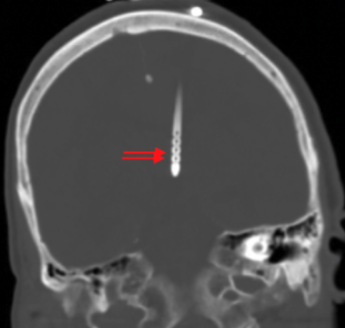

• window CTH to bone to see holes and make sure they are in vents

notion image